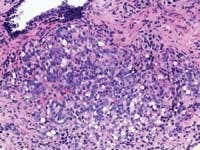

Gleason grading system; gene discovery

Zarbo: The issue of variation in pathologist interpretation of histologic biopsy secondary characteristics such as Gleason grade is well known. There exists the possibility of interobservor variation (e.g., between pathologists), as well as intraobservor (same pathologist) variation. Much of this variation can be diminished by standardization through education and training. For instance, the Johns Hopkins Pathology website provides a Gleason grading tutorial that may be helpful in illustrating images of critical grades, like grade 4, that may influence therapeutic decisions.

Tomaszewski: The Gleason grading system is the most powerful grading tool for the prediction of outcome amongst all the tumor systems. In almost every study ever performed, the Gleason grading system has statistically proven independent predictive value. Since, however, the Gleason grading system is a complex 10-level system, concordance levels in its application are only moderately good. The most critical threshold in the Gleason system is in the recognition of patterns 4 and 5. Once again, enhanced continuing medical education (CME) for pathologists is the most immediate remedy for improving the efficiency of patterns 4 and 5 recognition, and computer-assisted diagnosis (CAD) techniques could, in the future, facilitate this recognition. The public, however, must understand that even in the best of circumstances, the predictive power of the Gleason test is limited.